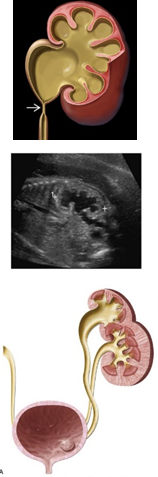

C. Invisible kidney

: 다음의 그림과 같이 sagittal view에서 renal fossa가 비어 있어 adrenal gland의 위치와 모양이 바뀌어 lying-down appearance를 관찰할 수 있습니다. 그 외 반대편 kidney는 hypertrophy해 보이며, coronal view에서 renal artery가 한 쪽이 없음을 같이 관찰할 수 있습니다.